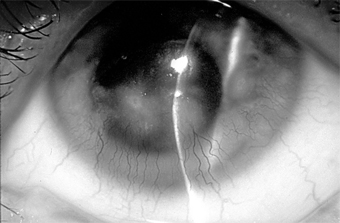

Treatment of ocular rosacea consists of the elimination of hot, spicy foods and of alcoholic beverages that cause dilation of the facial vessels. Any secondary staphylococcal infection should be treated (Figure 5-18). A course of oral tetracycline or doxycycline is often helpful, and a smaller maintenance dose may be needed to control the disease.

Figure 5-18

Figure 5-18: Multiple concretions on the inferior tarsus. These are often associated with chronic lid disease caused by staphylococcal species.